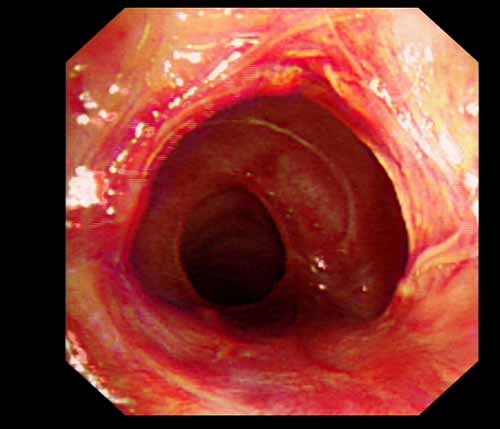

患者李某某,女,45歲,因氣管插管咳嗽、喘憋10天入院。頸部CT檢查示聲門下約20mm處氣管明顯狹窄,狹窄段長約26mm,最窄處直徑約4.4mm。支氣管鏡檢查見聲門下約2cm氣管呈漏斗狀縮窄,直徑約4-5mm,支氣管鏡無法通過。經科室討論,決定行電子支氣管鏡下氣管球囊擴張治療。與患者及家屬充分溝通并經三方見證談話簽署知情同意書后,在患者持續吸氧、局麻下,科主任于世倫主任醫師帶領治療小組為患者實行電子支氣管鏡下氣管球囊擴張術。手術過程順利,出血量很少,術后患者呼吸困難癥狀即可明顯緩解。10天后行二次擴張,患者日常活動無明顯喘憋,二次術后5天出院。

術后擴張開的氣管管腔